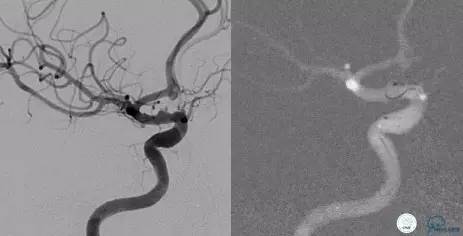

术前VS术后即刻

导管塑形